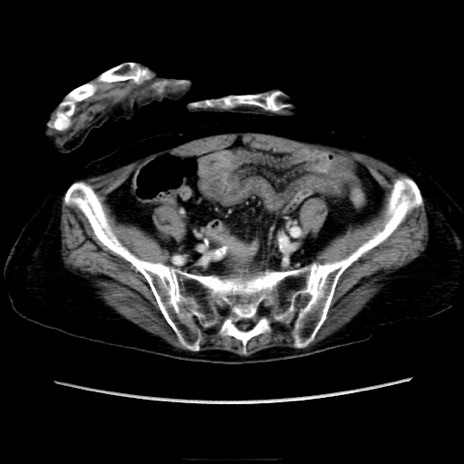

症例40(横断像)

【症例】90歳代女性

【主訴】腹痛・嘔吐

【現病歴】 食欲低下、嘔吐があり昨日他院受診。肺炎と診断され入院となる。入院後より腹部全体に圧痛あり。胃管留置され経過みていたが、症状持続するため、

当院転院となる。

【既往歴】胸椎圧迫骨折、胆石症

【身体所見】腹部:中央に激痛あり、圧痛あり、反跳痛不明

【データ】WBC 17100、CRP 18.82

横断像